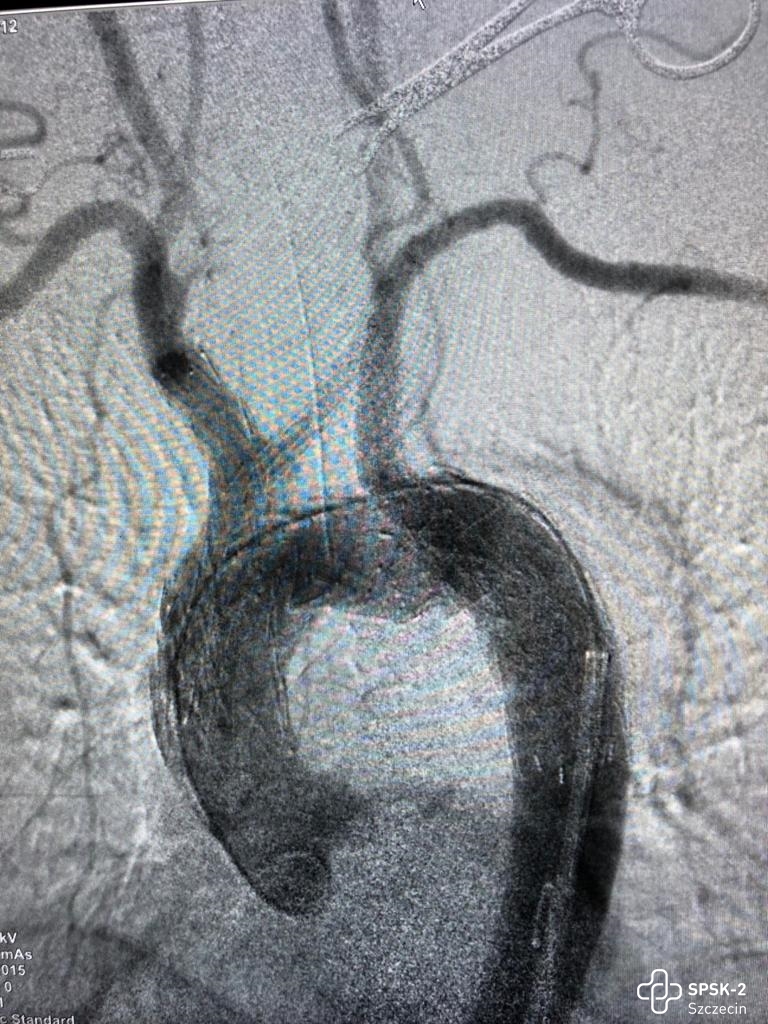

Dzień Zdrowia Aorty - przebadano ponad 40 osób

Badania przesiewowe aorty organizowane w ramach Dnia Zdrowia Aorty cieszyły się ogromnym zainteresowaniem. Pierwsi chętni do badań ustawili się w kolejce do zapisów już po godz. 8. U żadnej z osób nie wykryto tętniaka. Ta grupa pacjentów może spać spokojnie.

USG Dopplera aorty przeprowadzali dr n. med. Miłosz Kawa i dr n. med. Maciej Wojtuń. Grupą docelową, do której skierowane były badania były osoby po 65. roku życia, u których stwierdzono jednocześnie trzy spośród następujących czynników ryzyka sercowo-naczyniowego: choroba wieńcowa, palenie tytoniu, nadciśnienie tętnicze, hiperlipidemia, płeć męska, występowanie tętniaka aorty brzusznej u rodziców lub rodzeństwa czy przewlekła obturacyjna choroba płuc.

Oprócz badań USG chętni mogli zaznajomić się z najnowszymi metodami leczenia tętniaków aorty, obejrzeć filmy, w których nasi chirurdzy naczyniowi opowiadają o zagrożeniach chorobami naczyniowymi, zobaczyć na własne oczy czym jest tętniak i jak wygląda, obejrzeć wydrukowane w Ośrodku Technologii Medycznych 3D naszego szpitala modele organów człowieka, oraz poczuć się jak chirurg podczas operacji i dzięki goglom Hololens i wyświetlanemu w nich obrazowi rozszerzonej rzeczywistości ponawigować obrazem tomografii komputerowej i dokładnie obejrzeć struktury anatomiczne człowieka.

Nasi chirurdzy naczyniowi z Aortic Team znów pierwsi w kraju!

2022-11-07Lekarze Kliniki Chirurgii Naczyniowej, Ogólnej i Angiologii naszego szpitala dokonali pierwszego w kraju, całkowicie przezskórnego wszczepienia modyfikowanego stent-graftu. Była to operacja ratująca życie, a pomocna przy tym - technika druku 3D.

Dostępy całkowicie przezskórne (bez cięcia skóry) wykonuje tylko kilka ośrodków w Polsce i jest to metoda coraz częściej preferowana, ale głównie do mniej skomplikowanych przypadków. Tym razem do szpitala na Pomorzanach trafił 75-letni pacjent z objawowym tętniakiem okołotrzewnym (aorty piersiowo-brzusznej) - bolesnym, grożącym pęknięciem, a zatem stanowiącym zagrożenie życia. Dodatkowo chory nie miał szans na skorzystanie ze standardowego stent-graftu branchowego (z doszywanymi „rękawkami” na naczynia) czy fenestrowanego (z wyciętymi „okienkami” na naczynia) zamawianego u producenta z powodu występujących u niego dodatkowych naczyń, odchodzących od aorty (osobne ujście tętnicy wątrobowej). Nie mógł też czekać na wyprodukowanie stent-graftu szytego dla niego na miarę, bo trwałoby to 8-12 tygodni, a bolesność tętnika świadczyła, że rychło pęknie. Groziło to śmiercią pacjenta.

Leczenie stent-graftami modyfikowanymi jest w domeną naszych lekarzy Kliniki Chirurgii Naczyniowej, Ogólnej i Angiologii, którzy wypracowali wysokiej jakości standard postępowania w użyciu tej metody. Wykorzystując model aorty danego pacjenta, wydrukowany techniką 3D, modyfikują własnoręcznie, już na sali operacyjnej standardowe stent-grafty i dopasowują je indywidualnie do anatomii operowanego pacjenta. Po co? Bo mimo ogólnej takiej samej budowy każdego z nas, układ naczyń krwionośnych, ich budowa, odległości między poszczególnymi naczyniami różnią się u każdego człowieka. Dlatego dla efektywności działania wszczepianego, standardowego stent-graftu – proteza ta powinna być dopasowana do budowy chorego. Chirurdzy naczyniowi USK-2 są jedynym zespołem w Polsce, który tego typu zabiegi wykonuje rutynowo, również w przypadkach nagłych. Jednak taki sposób leczenia, jak i wszelkie inne zaawansowane procedury aortalne, wymaga licznych, często trudnych dostępów naczyniowych (np. nacięć w pachwinach, rękach i klatce piersiowej) – tj. cięć i operowania „na otwarto”. Dla chirurga taka operacja jest łatwiejsza, bo pole operacyjne jest widoczne jak na dłoni. Ale dla pacjenta dochodzenia do formy po takiej operacji jest długotrwałe, bolesne i mało komfortowe. Dlatego użycie przez szczecińskich lekarzy wyłącznie dostępu przezskórnego (bez cięcia) w leczeniu tętnika jest dużym krokiem na przód w chirurgii naczyniowej, a fakt, że to pierwszy tego typu zabieg w Polsce to ogromny sukces naszych „naczyniowców” i świadczy o ich doskonałej technice operowania.

„Modyfikacja stent-grafu naszą, ‘szczecińską metodą’ pozwoliła na pokonanie technicznych trudności, dostosowanie protezy do chorego i wykonanie zabiegu „od ręki”. Zastosowaliśmy modyfikację stent-graftu z okienkami na cztery naczynia trzewne - mówi dr hab. n. med. Arkadiusz Kazimierczak, który wraz z dr. n. med. Pawłem Rynio operował mężczyznę. „Wykonanie przezskórne - dwa dostępy do tętnicy podobojczykowej na klatce piersiowej i obu udowych w pachwinach, zamiast jak dotychczas czterech - pozwoliło na zminimalizowanie urazu operacyjnego tak, że chory był w pełni uruchomiony już w pierwszej dobie po zabiegu i zapytał o termin wypisu ze szpitala – dodaje dr Paweł Rynio. Operacja odbyła się 20 września.

Obaj lekarze są członkami szczecińskiego Aortic Teamu, zespołu chirurgów naczyniowych i kardiochirurgów stosujących nowatorskie metody leczenia w przypadku tętniaków. Zespół planuje rozszerzenie wskazań do zabiegów całkowicie przezskórnych w leczeniu patologii łuku aorty. Pierwsze próby z ograniczeniem urazu operacyjnego w tym zakresie zostały już podjęte w przypadku innej operowanej chorej. Tym razem zastosowano dwa małe cięcia przy wymianie całego łuku aorty, zamiast jak dotychczas pięciu. Pacjentka również jest w dobrym stanie.

Tłumacząc obrazowo - tętniakiem aorty nazywany nadmierne (o ponad 50%) poszerzenie aorty, która jest największą tętnicą w ciele człowieka. Może ono występować na każdym jej odcinku, ale najczęściej występuje w części brzusznej. Przyczyną ich powstania jest odkładanie się blaszek miażdżycowych, nadciśnienie tętnicze, nadmierny, gwałtowny wysiłek czy uraz, czasem także wrodzone nieprawidłowości w budowie naczynia. Ryzyko wystąpienie tętniaka aorty brzusznej wzrasta z wiekiem i jest szczególnie wysokie u mężczyzn około 65. roku życia. Szczególnie niebezpieczne są tętniaki bezobjawowe, które w każdej chwili mogą grozić pęknięciem i prowadzić do zgonu chorego.